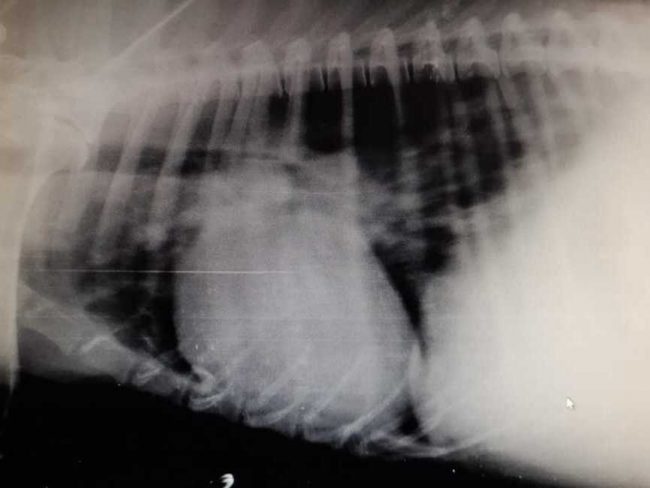

Гарик – довольно молодой и очень ласковый пес с человеческим взглядом, в тяжелейшем состоянии – истощен, асцит, дирофиляриоз, сердце просто «в хламе» – в клинике.

К сожалению, пока предварительный диагноз – Дилатационная кардиомиопатия, Асцит… Нет слов…

…Гарика отвезли сегодня в клинику. Он, конечно, очень тяжелый. С завтрашнего дня начинают обследование. Его старенькую маму Тину отвезем в понедельник, там серьезная опухоль.

Все анализы взяли, через 3 дня будет ясно, что по дирофиляриозу.